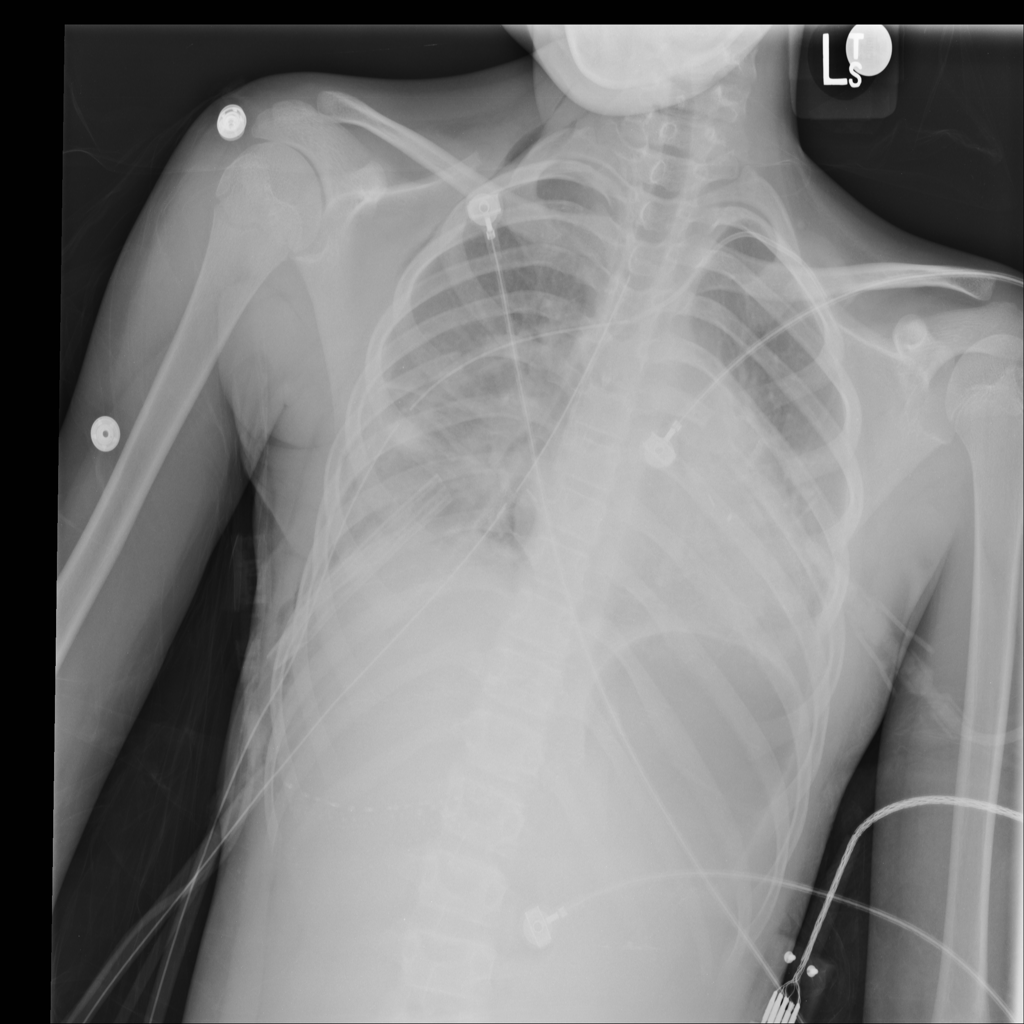

PAT-894B · IMG-000Emphysema

PAT-894B · IMG-000

PA